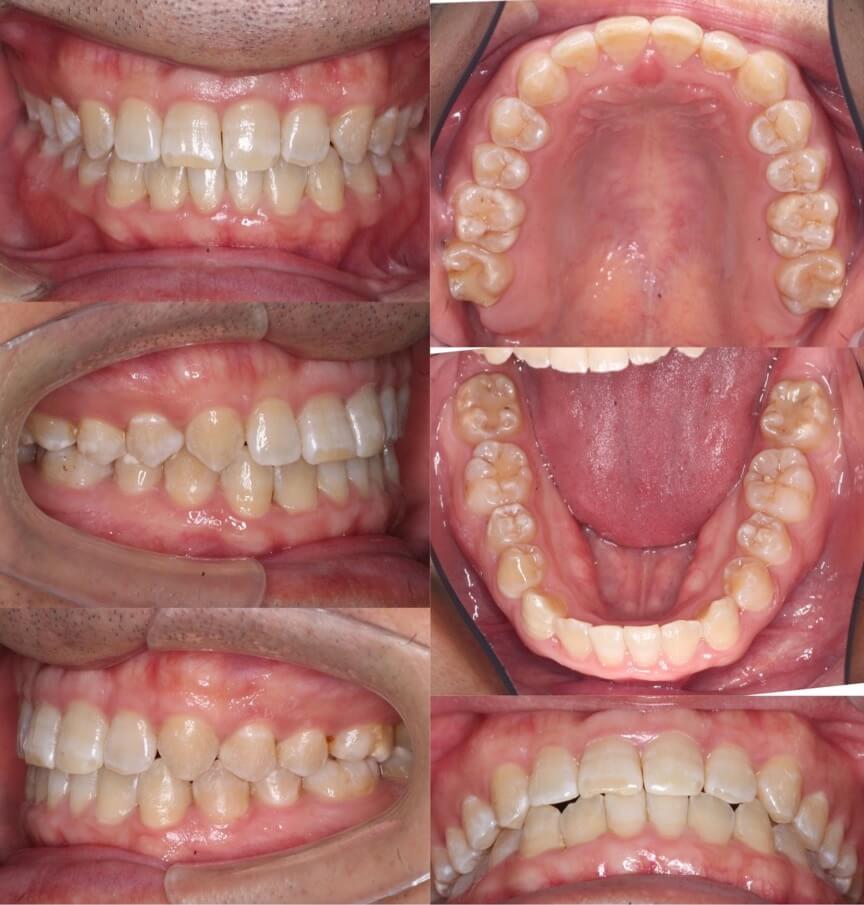

20代男性・唇側矯正装置・上下抜歯

前歯は完全に反対咬合になってはいないのですが、下あごが大きく切端咬合になっているケースです。片側に八重歯があり正中線がずれています。抜歯空隙をうまく利用して改善しました。

<症例概要> 難易度 ★★★★☆

主訴:下の前歯の突出

年齢・性別:20代男性

住まい:千葉県香取郡

症状:切端咬合・重度叢生・正中線不一致

治療方針:上下小臼歯抜歯・空隙閉鎖

治療装置:唇側矯正装置

固定装置:上バイヘリックス装置・III級顎間ゴム

抜歯:上第二小臼歯・下第一小臼歯(計4本)

治療期間:2年5か月

リテーナー:上下フィックスタイプ+プレートタイプ

治療費用:968,000(税込)

代表的副作用:痛み・治療後の後戻り・歯根吸収・歯髄壊死・歯肉退縮